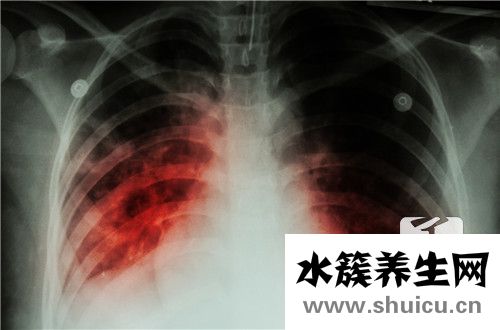

雙側(cè)胸膜增厚有很多原因,那么什么是雙側(cè)胸膜增厚呢?事實上,兩側(cè)胸膜增厚可能是由肺炎和肺結(jié)核引起的。肺炎患者必須記住不要拖延時間。他們必須及時接受常規(guī)治療,同時有合理的飲食。因此,讓我們分享一些適合肺炎患者的食物。